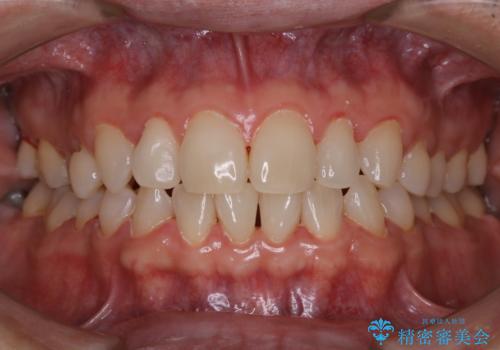

結婚式前にクリーニング希望の方